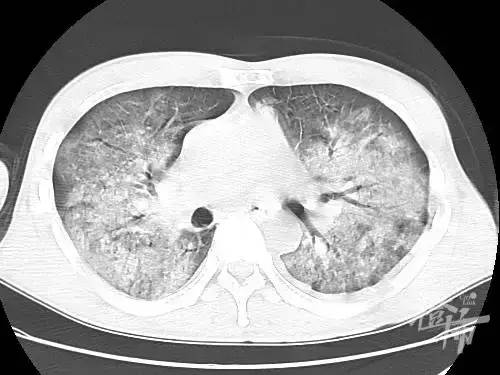

(李先生CT显示双侧白肺)

当时李先生已经是双侧白肺状态,属于典型的急性呼吸窘迫综合症,情况十分危急,已经无法耐受麻醉,为了提高抢救成功率,朱侠凯第一时间做了清醒气管插管,并用滴定方法找到最合适患者的通气模式。